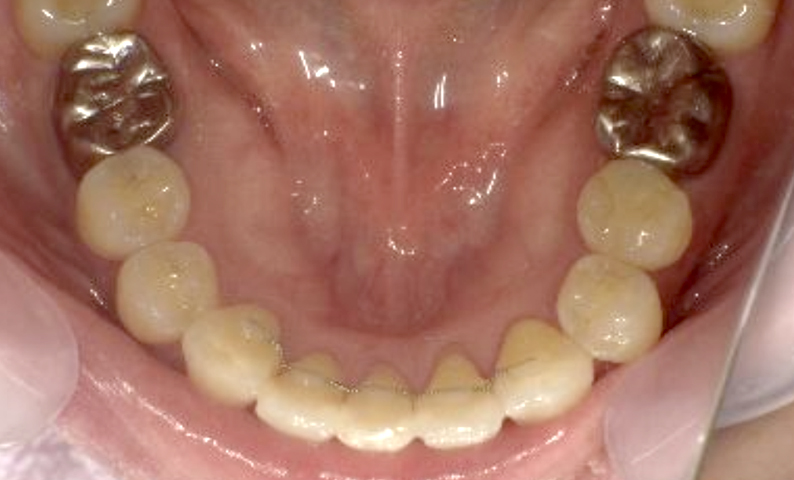

症例_001 下顎だけの部分矯正

治療期間:8ヶ月金額:21万円+税女性前歯のガタガタ下の前歯だけ

| Before | After |